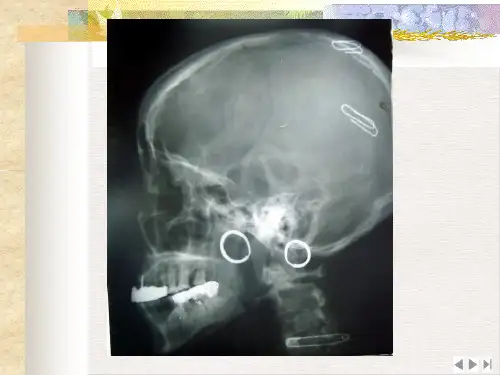

解剖结构识别通过观察不同切面的CT图像,可以识别头颅的各个结构,如颅骨、脑室、脑池、脑实质等。

头颅CT扫描范围头皮和颅骨通过头颅CT可以观察头皮和颅骨的形态、结构及骨折等病变。

显示脑实质密度、形态及脑沟回形态,判断是否存在脑水肿、脑出血等病变。

观察脑室大小、形态及脑室壁的厚度、密度,判断是否存在脑积水、脑室扩大等病变。

观察颅底骨质结构及脑脊液充盈情况,判断是否存在颅底骨折、脑脊液漏等病变。